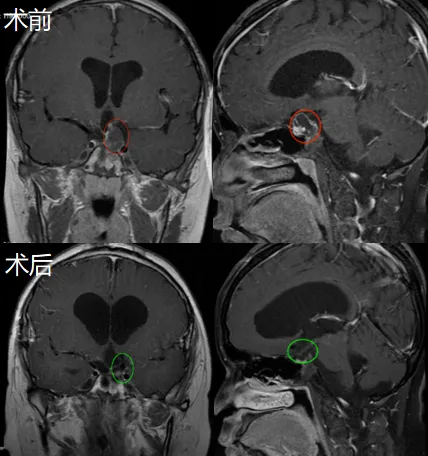

儿童颅咽管瘤的治疗目标到底是追求全切还是功能保留?目前医学界的普遍看法是,应该更侧重于患儿的生活质量而非肿瘤的根治性切除,因此,通常会建议次全切除加放疗的治疗模式,从而避...

在儿童神经外科领域,造釉细胞瘤性颅咽管瘤(AC)是个特殊的狠角色它虽被归为低级别恶性肿瘤,却因紧邻视路、垂体、下丘脑等关键结构,让治疗陷入两难:彻底切除可能导致终身内分泌紊...